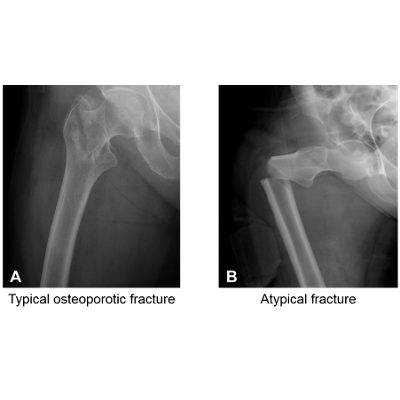

Bone Fractures

This NCLEX review will discuss bone fractures. As a nursing student, you must be familiar with bone fractures along with how to care for a patient experiencing one.